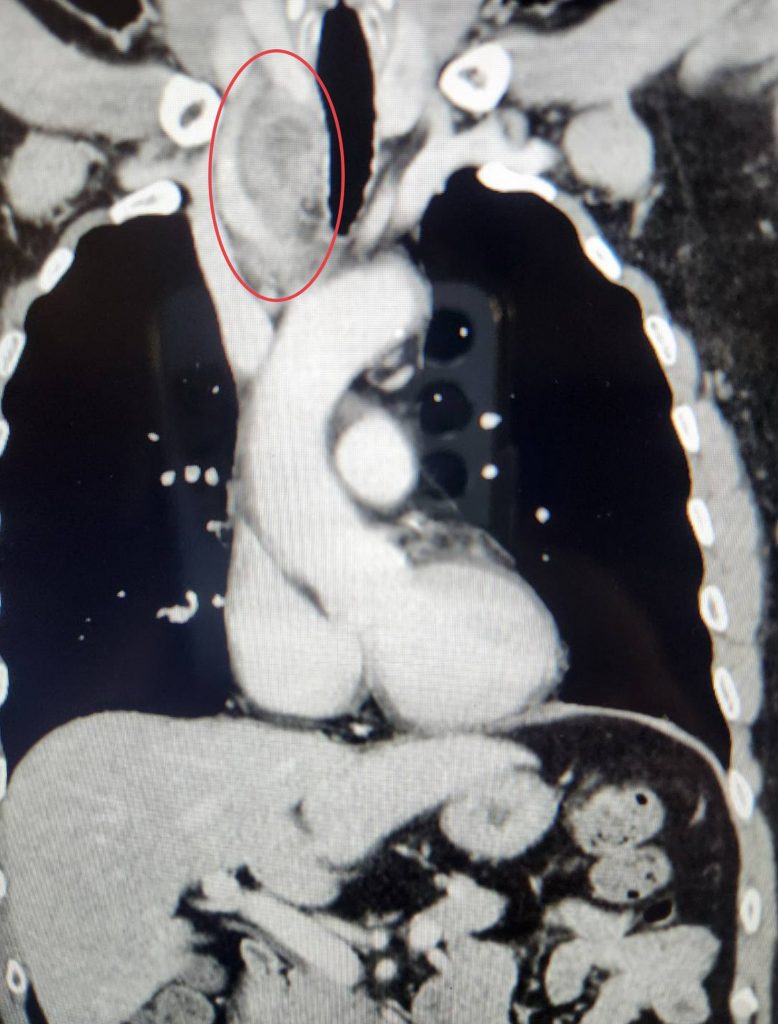

這位男性患者過往沒有特殊疾病史,除了扁桃腺紅腫、齒齦發炎,無其他明顯不舒服症狀,在他院接受抗生素治療,檢查過程驚見他的頸部到胸腔有1顆長邊達7.5公分的巨大腫瘤,已壓迫造成氣管嚴重向左偏移,原診斷認為是甲狀腺起源之腫瘤,但轉診在中港澄清醫院再做一次電腦斷層影像檢查,更像是神經來源的腫瘤,在外科部主任賴重佑專業評估及檢查影像結果判斷下,擬定治療方案。